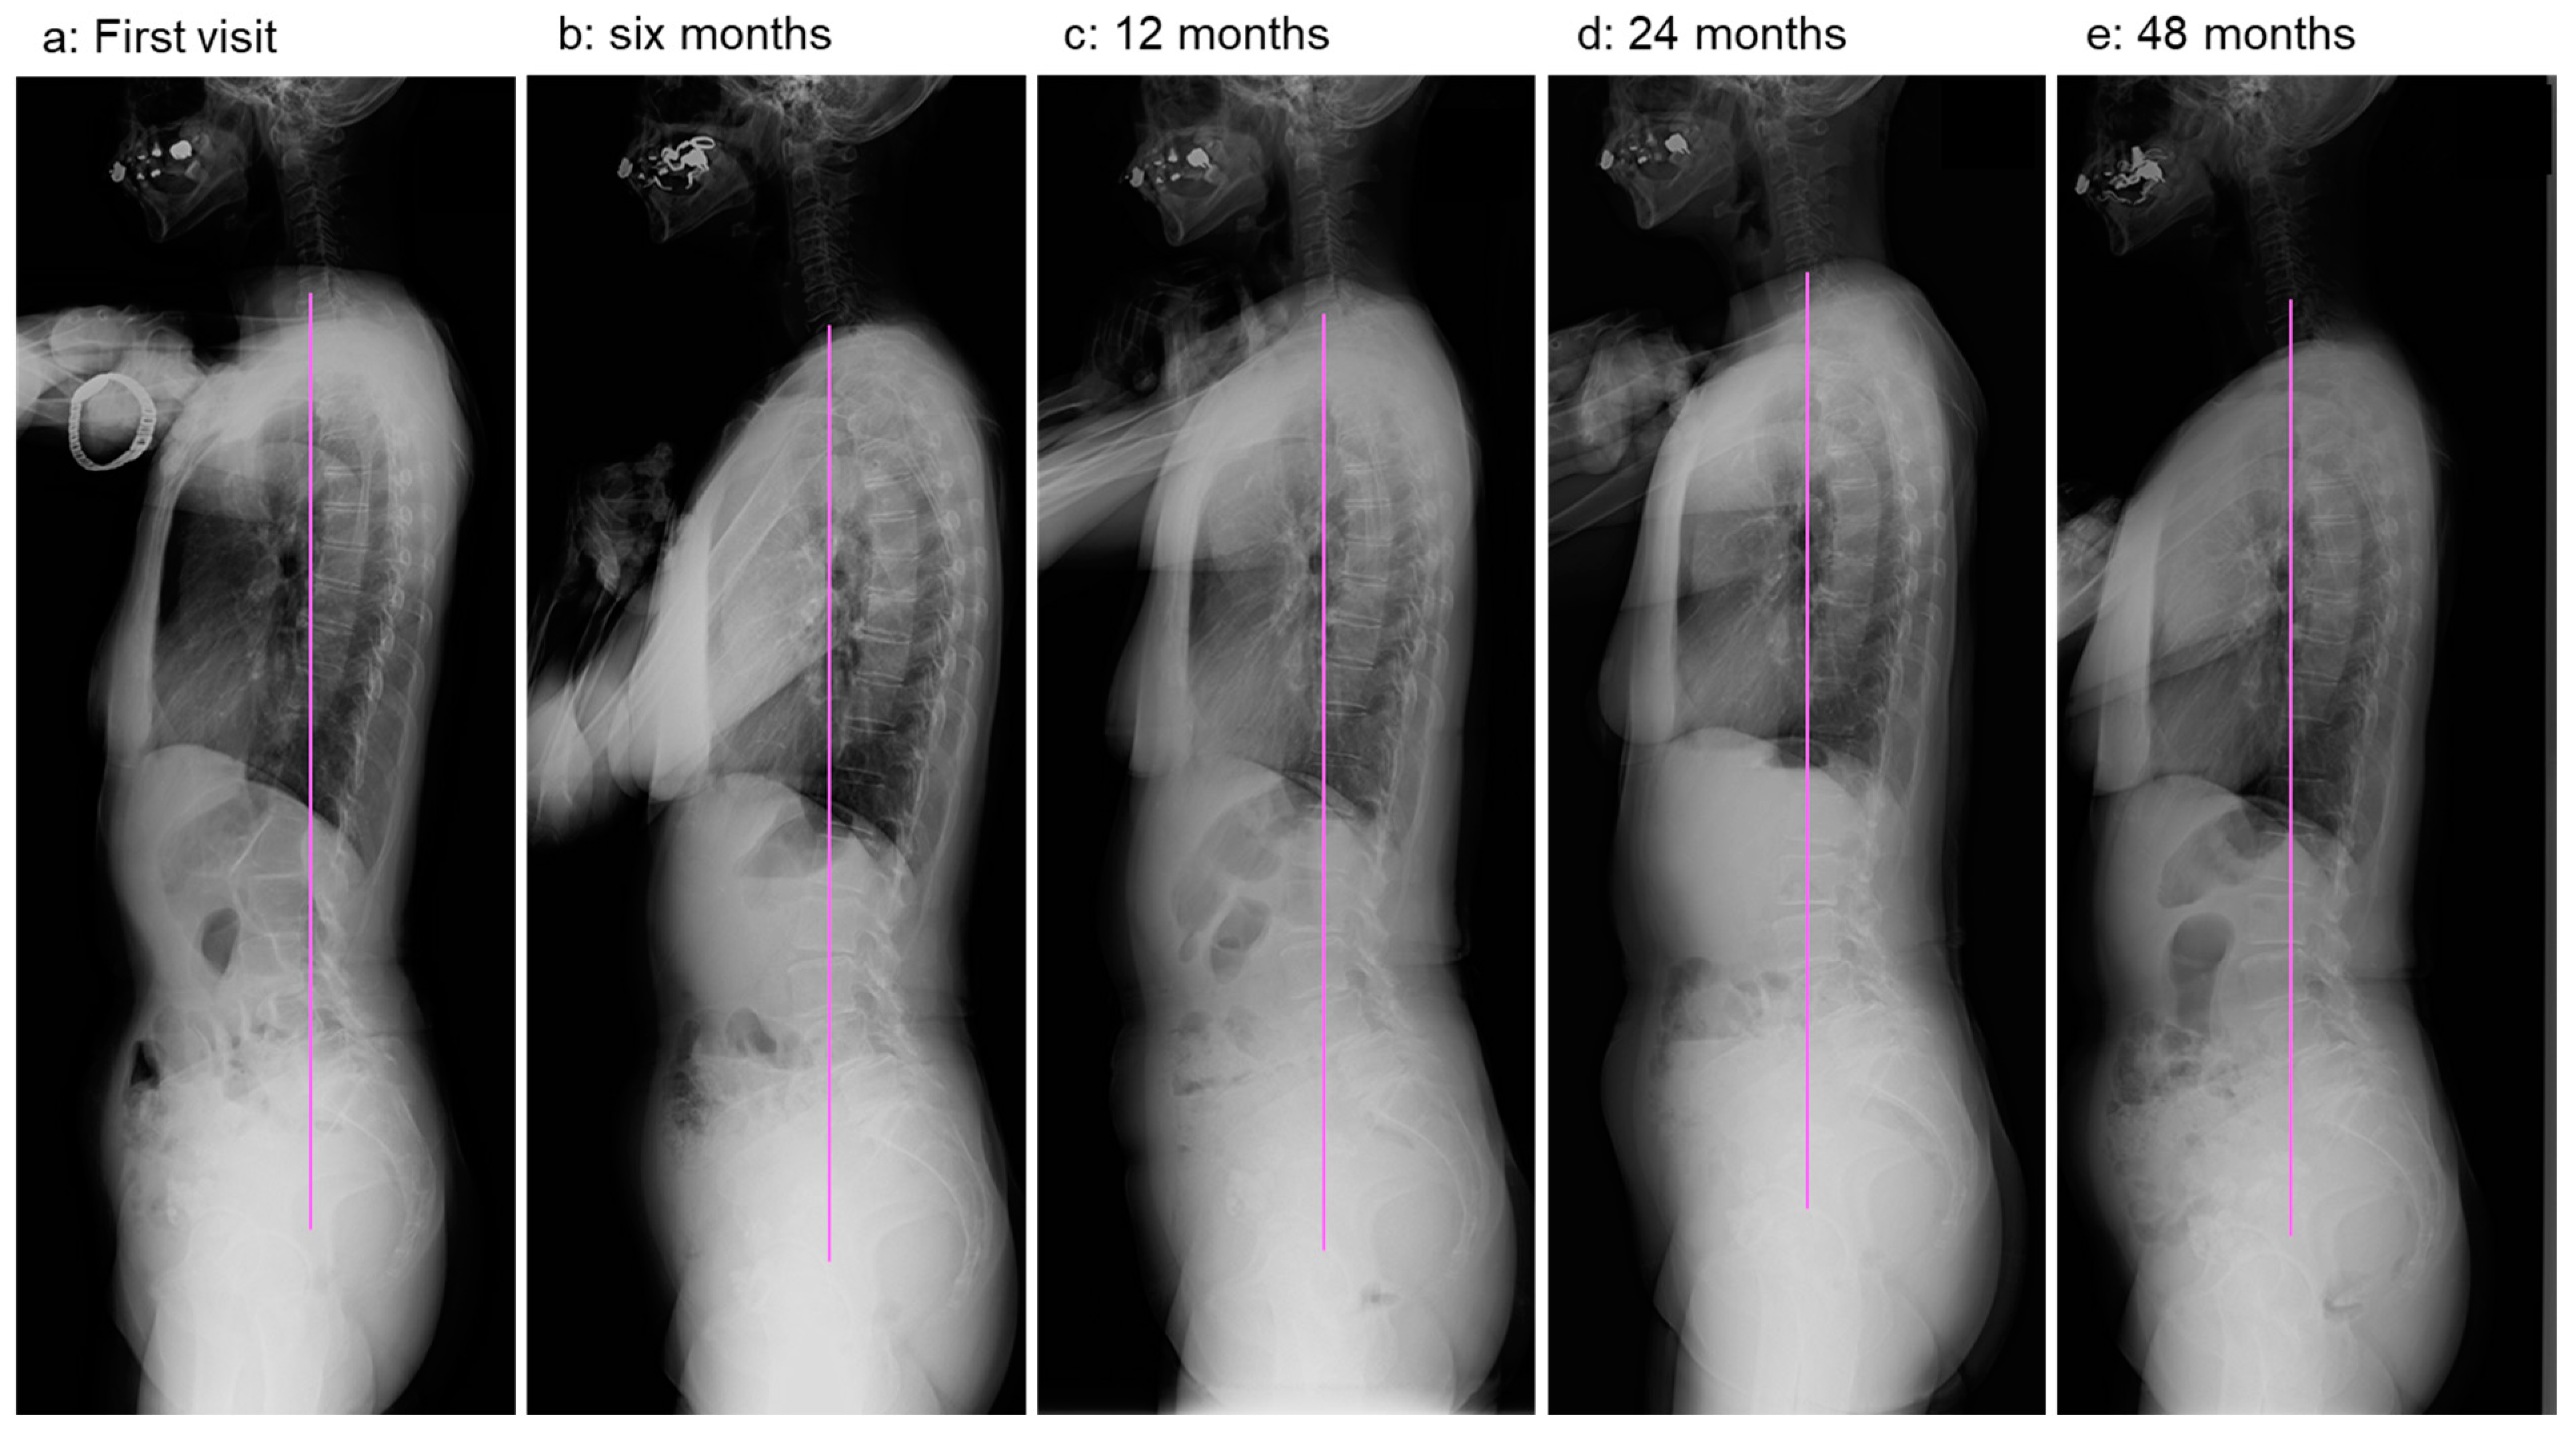

2.2. Image Examinations at First Visit

2.4. Image Examinations after Six Months of Daily Physical Exercise